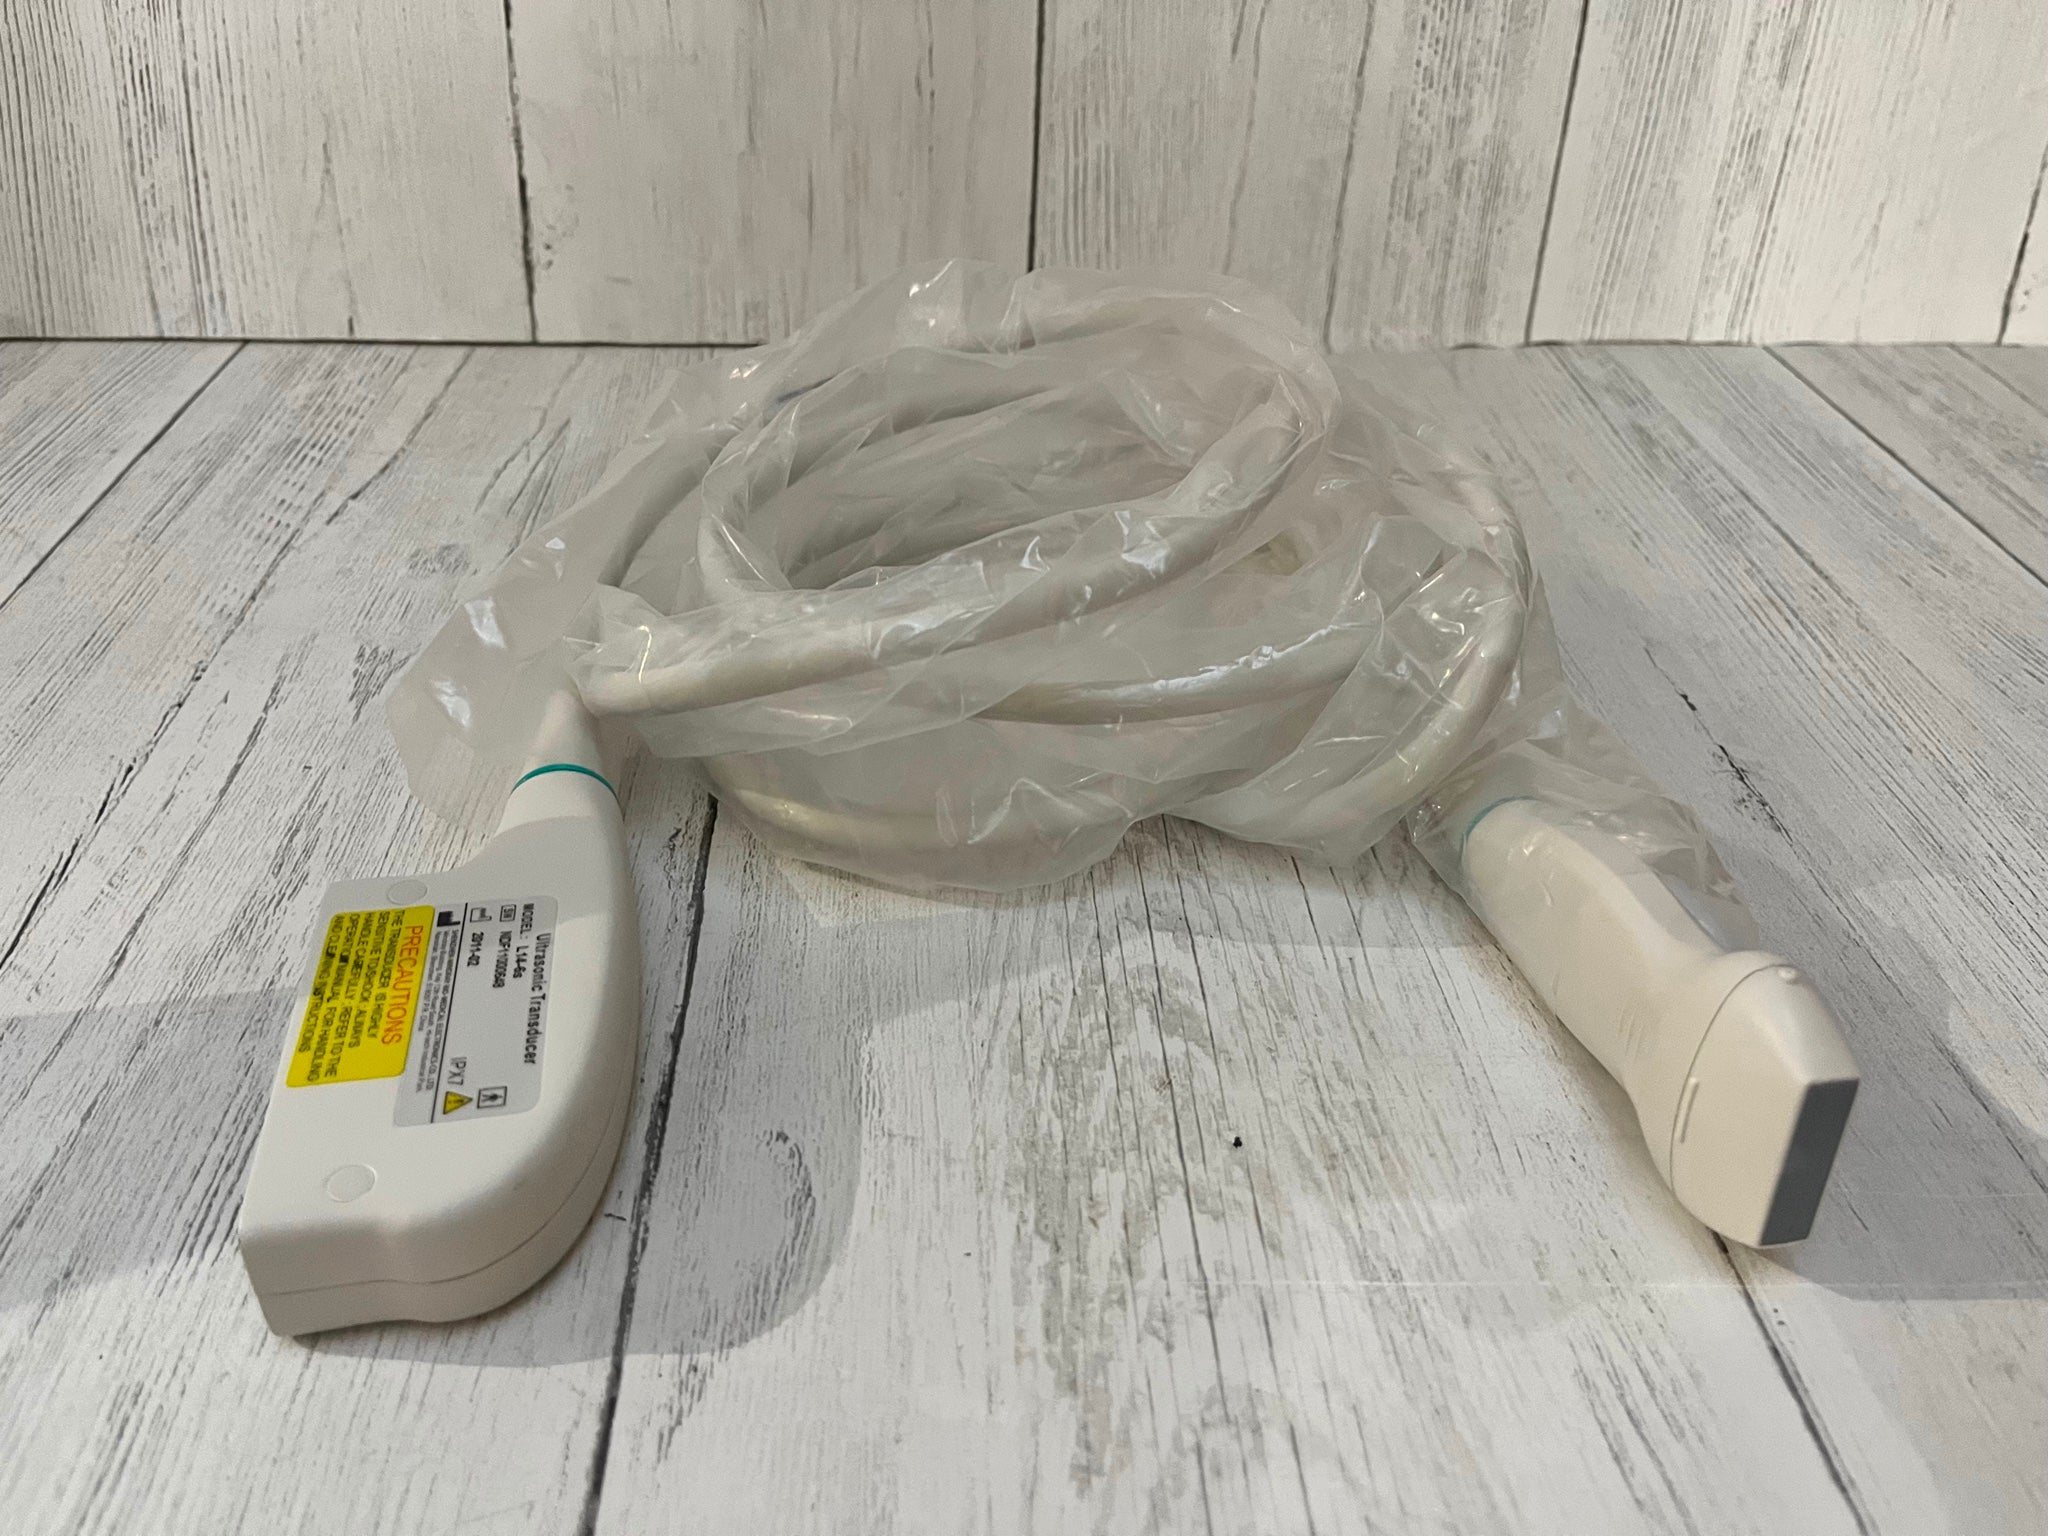

Optional: 3.5MHz R60 convex probe

7.5MHz linear probe: 6.5MHz Trans-vaginal probe

5.0MHz Micro-convex probe: Video Printer Sony UP-897